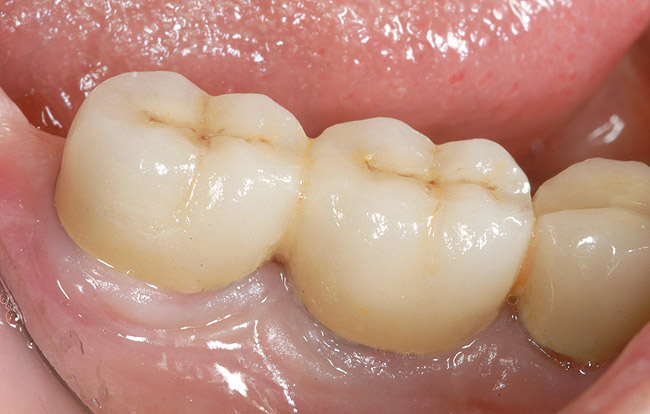

Figure 1  Replacement of a missing tooth has long been a treatment objective to improve oral health and function.

Figure 1